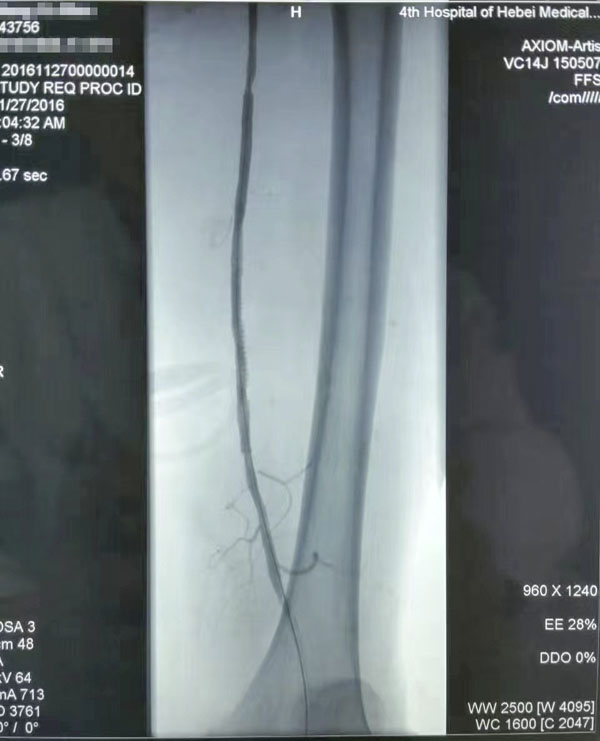

介入治療前后對比

糖尿病足重在預防,而預防和治療下肢血管病變是防治糖尿病足的有效措施。下肢血運重建是糖尿病下肢血管病變治療的根本采用球囊擴張開通狹窄或閉塞的下肢動脈(介入治療),恢復直達足部的血流,是治療糖尿病下肢血管病變的根本措施,具有立竿見影的效果這也是近年來在糖尿病足診治方面取得的又一新進展,為廣大糖尿病下肢血管病變患者解除了痛苦使糖尿病足患者截肢率由34%降至4%。世界防治糖尿病日到來之際,希望廣大糖尿病患者關注糖尿病下肢血管病變,保護自己的雙足,做到早發現、早治療,提升幸福感快樂每一天。